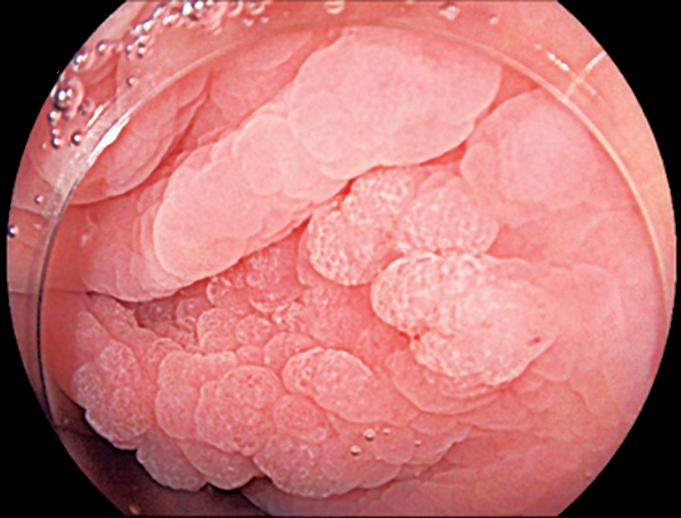

Evaluación endoscópica e histológica

La endoscopía superior es un procedimiento fundamental para el diagnóstico, la evaluación de la respuesta al tratamiento y el monitoreo a largo plazo de la actividad de la EEo. Los hallazgos endoscópicos típicos incluyen edema (reducción de vascularidad), anillos esofágicos fijos, exudados blancos, surcos longitudinales, estenosis, estrechamiento de la luz esofágica, friabilidad de la mucosa (mucosa en papel crepé) y una consistencia firme de la mucosa al realizar biopsias (signo de “tracción" o "resistencia”) en pacientes con fibrosis (Figura 1). Estos hallazgos no son patognomónicos y no constituyen un criterio diagnóstico; sin embargo, cuando se evalúa de forma cuidadosa, en la gran mayoría de los casos se pueden observar.19-21

En el panel A se observa un esófago con edema difuso y pliegues longitudinales; en el panel B se aprecia edema con pliegues y exudados blanquecinos; en el panel C se evidencia un estrechamiento luminal acompañado de anillos esofágicos y exudados; y en el panel D se muestra un desgarro mucoso posterior a la dilatación con bujía de Savary, hallazgo esperado tras este procedimiento terapéutico.

Figura 1. Características endoscópicas de la esofagitis eosinofílica